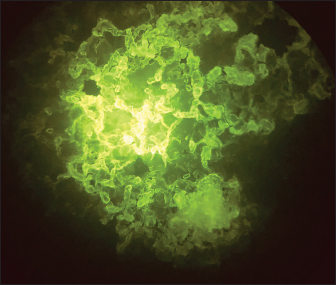

Direct fluorescent antibody technique (DFAT) carried out on brain impression smears from dead mice showed strong positive results represented by apple green spots confirming the presence of rabies (Fig. 2) with 90% positivity (9 out of 10 brain smears diluted up to 1:10,000 within 1–1.5 hours. A negative brain smear showed a negative reaction (Fig. 3) as a dark background. Application of DFAT on BHK-21 cell line inoculated with brain suspensions of infected mice showed intracytoplasmic apple green reactions in nine out of nine (100%) (Fig. 4), while normal cell culture did not show any fluorescent reaction (Fig. 5). This test needs 3–5 days to infect the cells and their preparation for DFAT.

Fig. 2. Positive DFAT carried out on brain impression of experimentally infected dead infected mice showing apple green spots.

The FITC-labeled antibodies to RABV are employed in the direct fluorescent antibody test, which is the gold standard for routine sensitive and specific lyssavirus postmortem identification (Mayes and Rupprecht, 2015). The FA test is also the most popular way to diagnose rabies infection in both humans and animals since it is reliable and results are frequently available within 30 minutes of receiving the specimen (WHO, 2018). In this study, the DFAT carried out on brain impressions of dead experimentally infected mice and infected BHK21 cell lines showed strong positive results with 90% and 100%, respectively, within 1–1.5 hours.